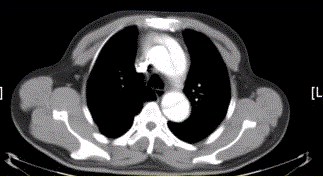

问题 患者男,67岁,高血压病史多年,自服降压药,突发胸骨后剧烈疼痛2h,服用硝酸甘油不缓解。胸透示主动脉增宽。CT影像如下图。 区分真腔和假腔最关键的征象是

选项 A.真腔通常较小 B.真腔通常位于前方 C.真腔通常血流速度慢 D.真腔的对比剂浓度通常高于假腔 E.真腔内常伴有血栓形成 F.真腔内有血管分支

答案 D